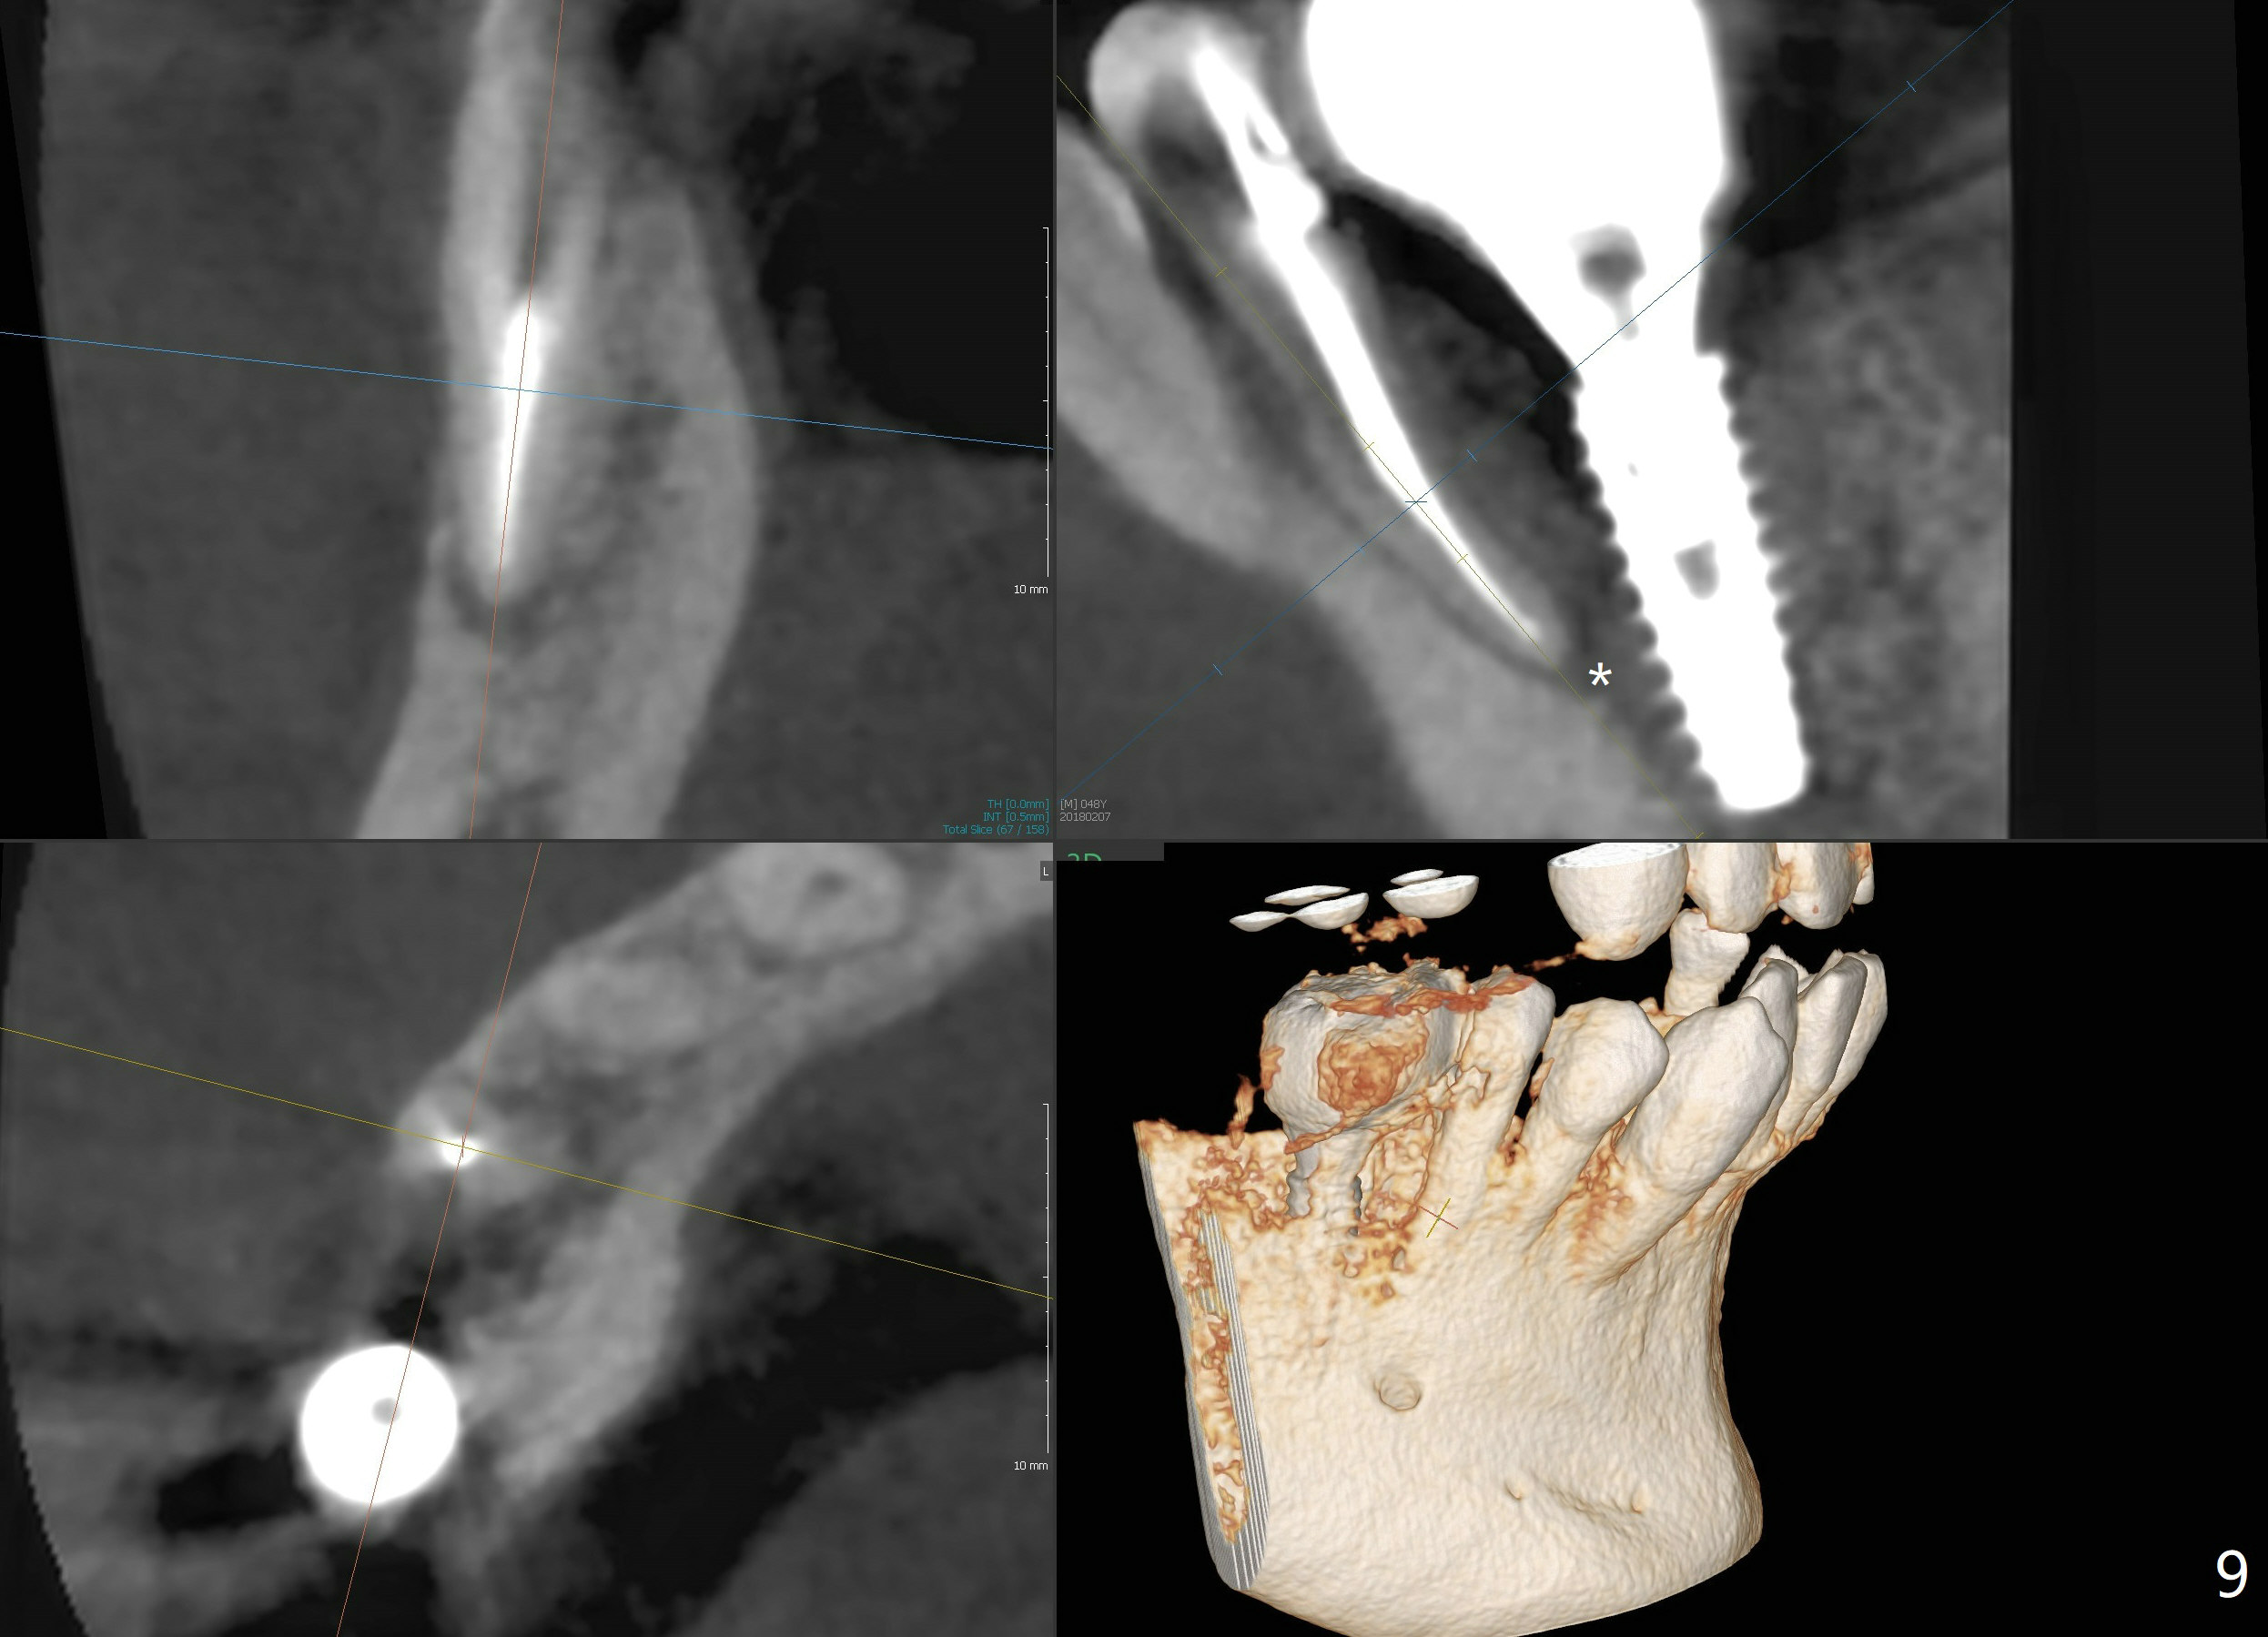

Bone graft seems to sink down and becomes denser 3 months postop (Fig.6 arrow). The bone continues being denser 5 months postop (Fig.7). There is periapical radiolucency of the tooth #29 (^). RCT is done (Fig.8). The pain persists 2 weeks postop (Fig.9,10). There is no missing canal (Fig.9). The apex is close to the implant (Fig.9 *). Apicoectomy will be performed if needed. It appears that the implant is also placed buccal (Fig.10 <) and/or the implant too large for the site. Therefore there should be a 2-3 mm buccal gap before and after implant placement. Separation and reflection of the buccal flap allows better visibility. The pain persists 1 month post RCT and 6 months post implant placement. RCT retreatment is initiated (Fig.11,12) with placement of Calcium Hydroxide paste after redebridement with 30/.04 rotary file at 23.5 mm (.5 mm longer than the earlier RCT, Fig.13). RCT retreatment finishes with apparent transportation and extrusion in 4 weeks (Fig.14,15), followed by apicoetomy (Fig.16,17) (20 days later)). Discomfort remains 2.5 months postop (Fig.18). Keep watching.